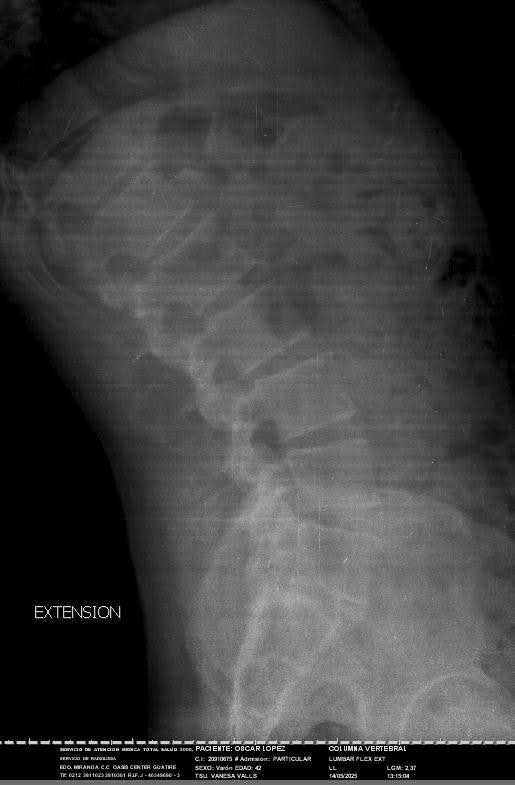

Hello, my name is Oscar. I am 43 years old. I am an orchestral trumpet player, for more than 15 years I was part of the Simon Bolivar Symphony Orchestra, representing Venezuela in thousands of concerts around the world. Today I need your help, due to the economic situation my country is going through, I cannot afford the materials for the arthrodesis I need for my spine surgery. I have been diagnosed with a lumbar disc herniation at the L4-L5 level, accompanied by grade I spondylolisthesis at the L5-S1 level. This has caused severe compression of the lumbar nerve roots, causing constant pain, loss of mobility, and paresthesia. My condition has been evaluated by the medical team, who has indicated the need for imminent spinal surgery.

• L4-L5 discectomy

• Decompressive laminectomy

• Placement of instrumentation (screws, rods, a cross connector, and a specialized cage)